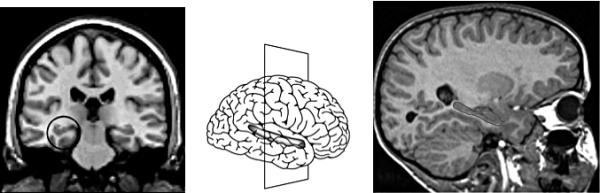

Иллюстрация к книге — Антимозг. Цифровые технологии и мозг [i_005.jpg]

1.1. Гиппокамп — парный орган, расположенный в медиальных височных отделах полушарий головного мозга. Слева показан гиппокамп в разрезе (секущая плоскость изображена на рисунке посередине). Справа — продольный разрез.